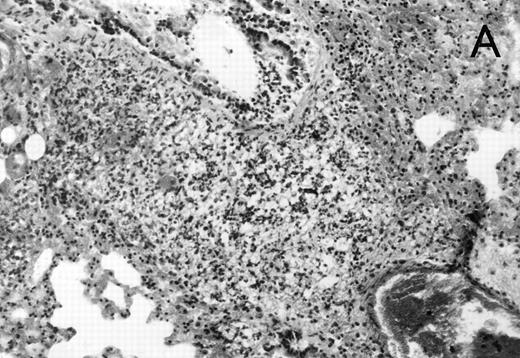

Histology further supported this observation. Control animals showed well-developed pneumonia with abscess formation (Fig3A) in their lungs, but in their livers, only small areas of inflammation with scattered microabscesses and foci of hepatic necrosis were observed (Fig 3B). In contrast, mice pretreated with G-CSF had only mild peribronchitic alterations in their lungs without signs of containment of inflammation such as abscess formation (Fig 4A). Livers and spleens of mice pretreated with G-CSF were severely altered, showing large abscesses which contained massive amounts of bacteria (Fig 4B). In addition, large necrotic areas surrounded by granulocytes were observed in the livers (Fig 4C). When MoAb III/5-1 was administered in addition to pretreatment with G-CSF, almost all changes observed in animals pretreated with G-CSF were reversed: there were only minor bronchial and peribronchial infiltrations by granulocytes (minimal change focal pneumonia), and the livers showed small microabscesses as observed in control mice. When treatment with G-CSF was started at 24 hours after bacterial challenge, a mixed pattern was observed. In the lungs, there was a beginning pneumonic reaction and a moderate perivascular and septal edema. However, in the liver there was almost no difference to the severe alterations observed in mice pretreated with G-CSF: huge abscesses loaded with bacteria joined extended necrotic areas.

(A) Micrograph of lung tissue 72 hours after intranasal infection with 1 × 103 CFU of K pneumoniae B5055. Lung abscess with severe tissue destruction in a PBS-treated control animal. Hematoxylin & Eosin (H&E); original magnification ×150. (B) Small foci of hepatic necrosis. H&E; original magnification ×600.

(A) Micrograph of lung tissue 48 hours after intranasal infection with 1 × 103 CFU of K pneumoniae B5055 and pretreatment with G-CSF (50 μg/kg sc) at −48 hours, −36 hours, −24 hours, and −12 hours before infection. Peribronchiolar neutrophils without destruction of lung parenchyma. H&E; original magnification ×150. (B) Splenic abscesses in the red pulp containing numerous gram-negative bacilli are found. H&E; original magnification ×370. (C) Confluent hepatic necroses. H&E; original magnification ×150.